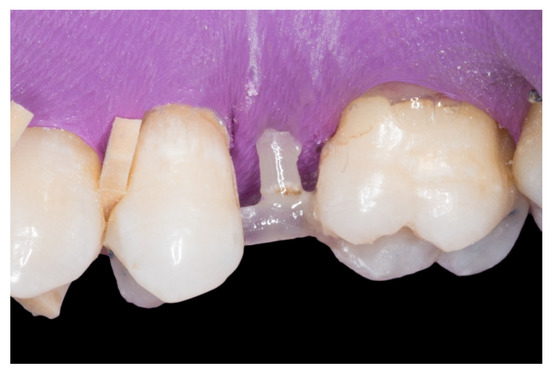

Figure 1.

A posterior maxilla edentulous space.

1. The new technique in “T” started once the silicone impressions of the patient were taken for both arches, and an interocclusal registration in the maximal intercuspation position was obtained, in order to prepare (on an articulator) the wax-up and the silicone keys for the tooth replacement [20]. Figure 1 represents the initial state of a case collected in the study.

2. The proximal faces of the adjacent teeth delimiting the edentulous space were carved up to the level of the ideal point of contact (inlay cavities), to position the future horizontal structure of the fiberglass bridge (Figure 2).

3. The next step consisted of the horizontal fiberglass pin (Rebilda® Post GT, VOCO GmbH, Cuxhaven, Germany) bonding to the adjacent teeth. Firstly, when the isolation of the operative field with the rubber dam was made, the fiberglass pin was adjusted to size and silanization according to the instructions by the manufacturer. Later, the inlay cavities were etched with Ultra-etch® (Ultradent Products Inc, South Jordan, UT, USA) for 20 s, rinsed for 10 s and dried for 10 s. The etched surfaces were covered with a layer of a universal adhesive resin (Prime & Bond® NT, Dentsply Sirona Inc., York, PA, USA), thinned using a brush, and cured for 20 s with a light- polymerizing unit. A flowable resin (Tetric Evo flow®, Ivoclar Vivadent AG, Schaanwald, Liechtenstein) was used to cover the inlay cavities (inlays retainers) and the fiberglass pin to shape the transverse structure of the future bridge (Figure 3 and Figure 4).